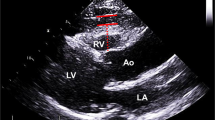

Echocardiography and measurement of EpF

Left atrial (LA) diameter, the LV end-diastolic and systolic diameters, interventricular septum thickness, LV posterior wall thickness, mitral inflow early rapid filling wave (E), peak velocity of the late filling wave due to atrial contraction (A), E/A ratio, E wave deceleration time, and mitral annular early diastolic velocity were measured according to the American Society of Echocardiography guidelines using an iE33 xMATRIX echocardiography system (Philips Healthcare, Best, the Netherlands). The LV mass index was calculated from the LV end-diastolic and systolic diameters, interventricular septum thickness, and LV posterior wall thickness according to the method of Devereux et al.[21]. The peak annular early and late diastolic velocities of the lateral mitral annulus during tissue Doppler imaging (e’ and a’) were also recorded. Doppler and color Doppler studies were performed to detect valvular heart disease. Significant valvular heart disease was defined as at least moderate aortic or mitral stenosis/regurgitation. EpF was measured by 2 readers with no knowledge of the patients’ baseline characteristics according to previously published methods[22]. In brief, EpF was identified as the echocardiographically free space between the outer wall of the myocardium and the visceral layer of the pericardium, and its thickness was measured perpendicularly to the free wall of the right ventricle at end-systole over 3 cardiac cycles (Figure 1). The mean value of 3 cardiac cycles from each echocardiographic view (including both parasternal long- and short-axis views) was recorded as the EpF thickness. Repeat analysis of 20 patients was performed by either the same or a second observer. Inter-observer correlation coefficients were 0.89 whereas intra-observer correlation coefficients were 0.93.